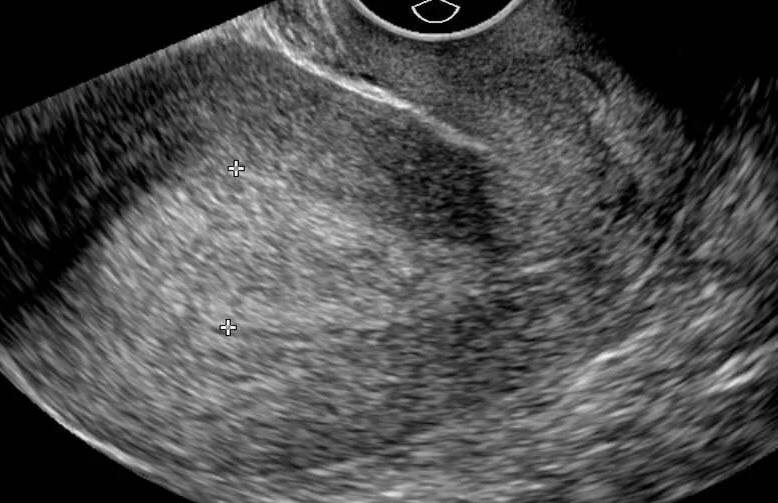

Диагноз ГЭ устанавливается на основании жалоб на АМК, анамнеза, физикального обследования, заключения ультразвукового исследования.